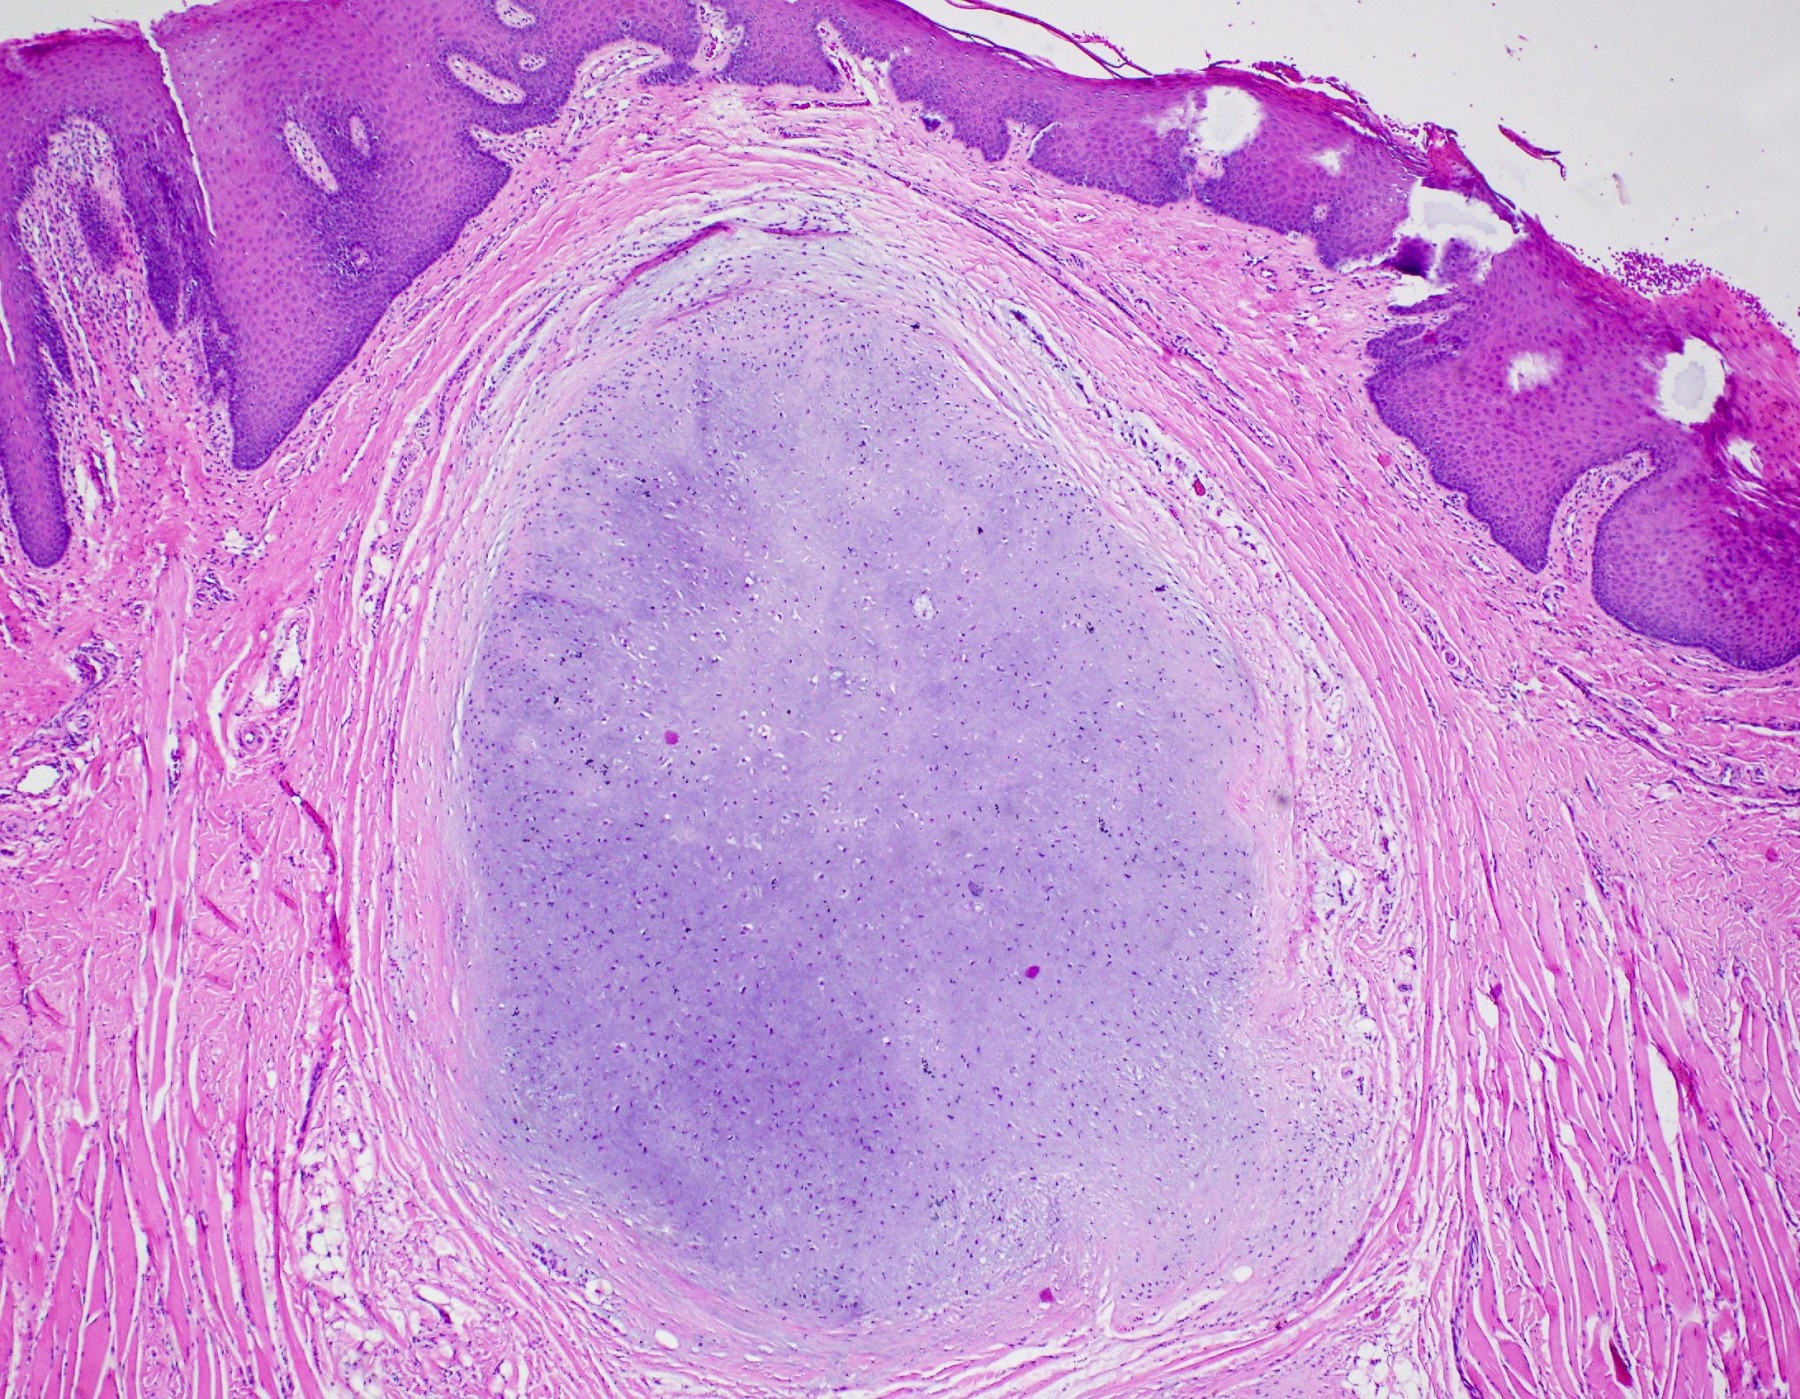

Microscopic (histologic) description

- Well demarcated tumor, often entrapped within skeletal muscle and frequently multilobulated (Am J Surg Pathol 2018;42:1297, Head Neck Pathol 2015;9:315)

- Stromal background may be hyalinized or demonstrate mucoid, myxoid or chondromyxoid areas

- Cords, strands or sheets of oval, round, fusiform or polygonal bland cells, sometimes arranged in a reticular / net-like or globoid pattern (Am J Surg Pathol 2018;42:1297)

- Myxoglobulosis-like changes have been noted (Virchows Arch 2003;442:302)

- May focally demonstrate fine calcifications, cellular atypia, necrosis, multinucleated giant cells (Am J Surg Pathol 2018;42:1297, Head Neck Pathol 2015;9:315, Oral Surg Oral Med Oral Pathol Oral Radiol Endod 1996;82:417)

- Cystic, slit-like spaces or hemorrhagic areas often noted (Head Neck Pathol 2014;8:329)

- Mitotic figures not seen (Head Neck Pathol 2015;9:315)

Microscopic (histologic) images